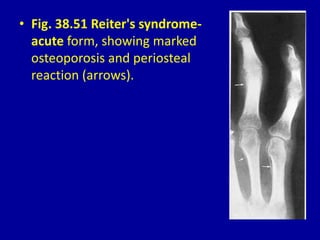

• Fig. 38.51 Reiter's syndrome-

acute form, showing marked

osteoporosis and periosteal

reaction (arrows).

• Fig. 38.51Reiter's syndrome- acute form, showing marked osteoporosis and periosteal reaction (arrows).